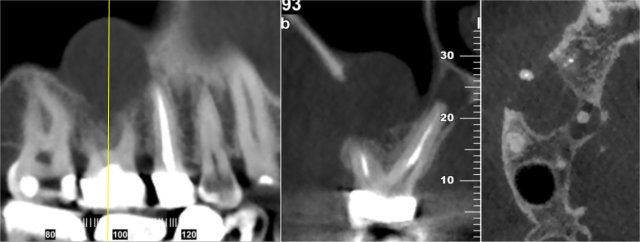

CBCT Endodontic Scan

Identify potential disease, infection, and abnormalities that surround adjacent teeth.